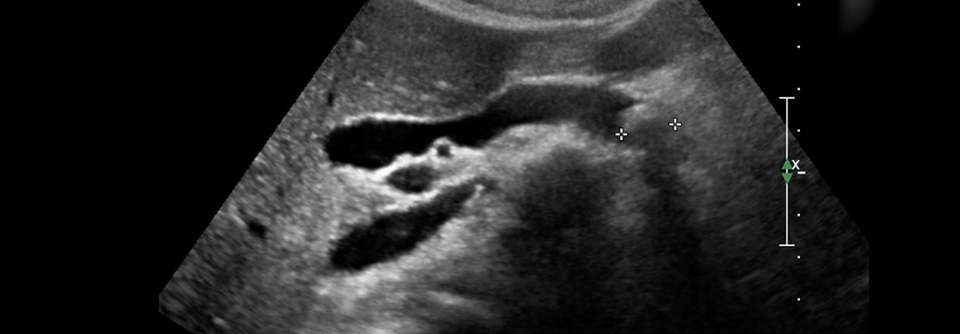

In einer Studie mit transgenen Mäusen entwickelten die Tiere, die CA19-9 exprimierten, eine schnell fortschreitende und schwere Pankreatitis. Waren die Nager zusätzlich Träger des KRAS-Onkogens, erkrankten sie im Verlauf an einer aggressiven Form von Bauchspeicheldrüsenkrebs.